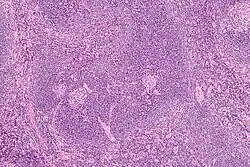

Histology of a normal secondary lymphoid follicle, with yellow arrows pointing at the mantle zone.

The mantle zone (or just mantle) of a lymphatic nodule (or lymphatic follicle) is an outer ring of small lymphocytes surrounding a germinal center.[1]

It contains transient lymphocytes.[3]

It is the location of the lymphoma in mantle cell lymphoma.

Intermediate magnification micrograph of Castleman disease showing the characteristic expansion of the mantle zone. H&E stain

Mantle zone expansion may be seen in benign, such as Castleman disease, and malignancy, i.e., Mantle cell lymphoma. Tcl-1 is expressed in the mantle zone.